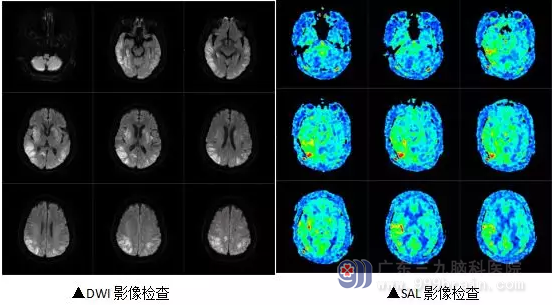

为明确病情,入院后,王展航为其完善了相关检查。我院MR弥散成像(DWI)显示患者双侧额颞岛顶枕叶、双侧基底节-左侧放射冠区多发弥散受限病灶;右侧基底节区陈旧性出血灶;我院MR灌注成像(ASL)显示患者双侧小脑半球、双侧额叶、左侧颞顶枕叶局部灌注减低;右侧颞岛枕叶局部灌注增高。结合病症及检查结果,最终明确诊断林阿姨是低血糖昏迷性脑病。